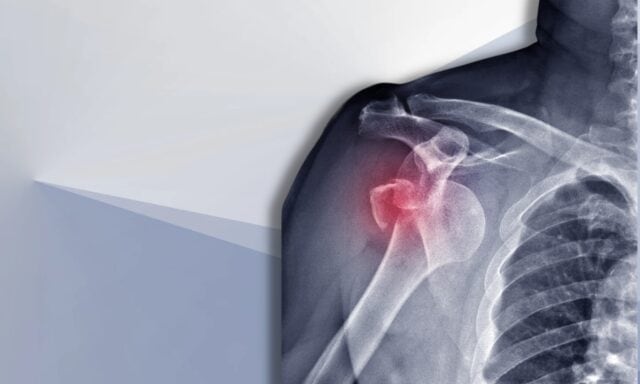

Tässä jaksossa puhumme kaikesta hartioiden epävakaudesta. Opit lisää Stanmore-luokittelusta ja rakenteellisista vaurioista dislokaatioiden jälkeen. Keskustelemme tyypillisestä olkapään epävakaudesta kärsivästä potilaasta ja siitä, miltä tutkimusprosessi näyttää. Käsittelemme lihasaktivaatiotapoja, leikkausta ja sitä, miltä olkapään epävakautta kärsivän potilaan fysioterapeuttinen hoito voisi mahdollisesti näyttää. Muista siis kuunnella koko jakso!